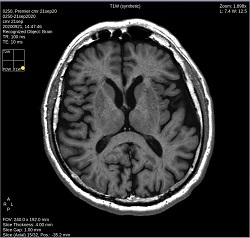

Table 1. Right-click menu to change image contrast in the active viewport Right-click selection Right-click selection Click T1W to change the image contrast to synthetic T1-weighted.

Click T2W to change the image contrast to synthetic T2-weighted.